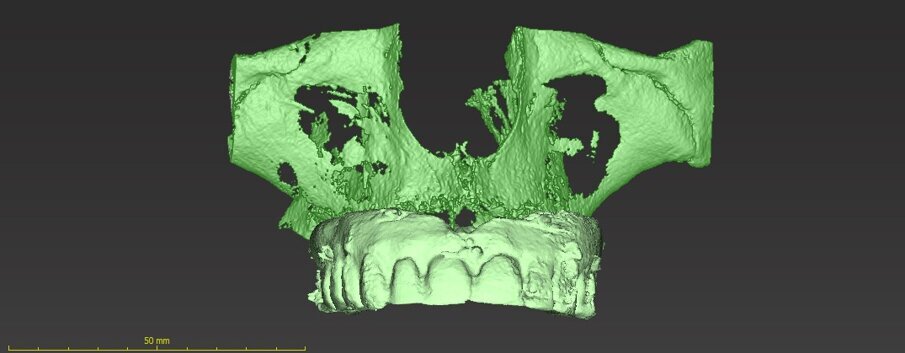

Nei casi di atrofie marcate, è fondamentale ricostruire l’osso mancante ma anche poter dare all’arcata una forma ideale. In questo caso clinico la paziente si presenta alla mia osservazione con una marcata atrofia del mascellare superiore (Fig. 1). La valutazione clinica è stata effettuata con esami radiografici di routine, OPM ed endorali, ma soprattutto con una Cone Beam TC. Da alcuni anni infatti, effettuo tutte le valutazioni diagnostiche in ambiente CAD con un software di chirurgia computer guidata che consente di valutare l’osso residuo in relazione al posizionamento tridimensionale dell’impianto protesicamente guidato.

L’approccio è quello di duplicare la protesi mobile utilizzata quotidianamente dalla paziente per renderla, attraverso punti di repere radiopachi, protesi radiologica. La paziente eseguirà la Cone Beam con la protesi radiologica e grazie alla presenza dei punti di repere radiopachi si potrà fare il matching tra i dati DICOM e la protesi della paziente (Figg. 2-4). Durante questa prima valutazione risulta evidente l’assenza di osso attorno agli impianti. La marcata perdita ossea è prevalentemente orizzontale e si estende in senso antero-posteriore su tutta l’arcata mascellare. Nella zona degli incisivi il posizionamento protesicamente guidato non è possibile a causa dell’assenza orizzontale dell’osso. Nelle zone posteriori inoltre si evidenziano i prolassi dei seni mascellari che riducono ulteriormente la disponibilità ossea. Di fronte a un quadro clinico così complesso si rende necessaria una scelta oculata della tecnica ricostruttiva adeguata.

Una volta ottenute tutte le informazioni necessarie dei dati ossei (Cone Beam), della pianificazione protesica (STL della ceratura, dei tessuti e della situazione iniziale) l’azienda (ReOss, Filderstadt, Germany) invia il progetto della griglia Yxoss CBR che può essere visualizzato in maniera tridimensionale ed eventualmente modificato a discrezione del professionista. Suggerite le eventuali modifiche si esegue la validazione finale del progetto per la realizzazione della griglia (Fig. 8).Con la Customized Bone Regeneration (CBR) l’obiettivo della Rigenerazione Protesicamente Guidata in senso digitale viene così raggiunto. Le griglie sono prodotte attraverso una stampa tridimensionale e il loro fit al difetto è sempre accuratissimo consentendo di concentrare l’attenzione alle altre fasi dell’intervento.

La chiusura dei lembi viene effettuata dopo aver posizionato una matrice Geistlich Mucograft (Geistlich Pharma) (Fig. 33) allo scopo di migliorare la qualità e la quantità del tessuto molle. Da questo momento in poi inizia la vera pianificazione degli impianti protesicamente guidati. I nostri riferimenti estetici e funzionali, in questo momento della terapia, sono quelli della protesi fissa ancorata ai tre impianti che la paziente ha portato per tutto il periodo post-operatorio. Scegliamo la strada del flusso totalmente digitale che darà innumerevoli vantaggi. Ripartiamo quindi dalle impronte digitali della situazione attuale per iniziare digitalmente a fare una ceratura che dovrà mantenere inalterati i rapporti tra le arcate, ma che avrà anche lo scopo di migliorare l’estetica (Fig. 34).

Inoltre da questa nuova ceratura dobbiamo ricavare una protesi radiografica con i punti di repere radiopachi che ci servirà per fare il matching con i nuovi file DICOM dell’osso rigenerato (Figg. 35, 36). Fatte le opportune verifiche nel software di chirurgia guidata, si pianifica l’intervento di posizionamento implantare (Figg. 37-40). Si programma lo stesso giorno della chirurgia anche il carico immediato degli impianti; decisione supportata dalla verifica istologica dell’osso rigenerato che dovrà comunque essere confermata il giorno del posizionamento implantare durante il quale si misurerà il torque di inserimento degli impianti e la stabilità primaria con il sistema OSSTELL mentor (Integration Diagnostics) che sfrutta l’analisi della frequenza di risonanza.